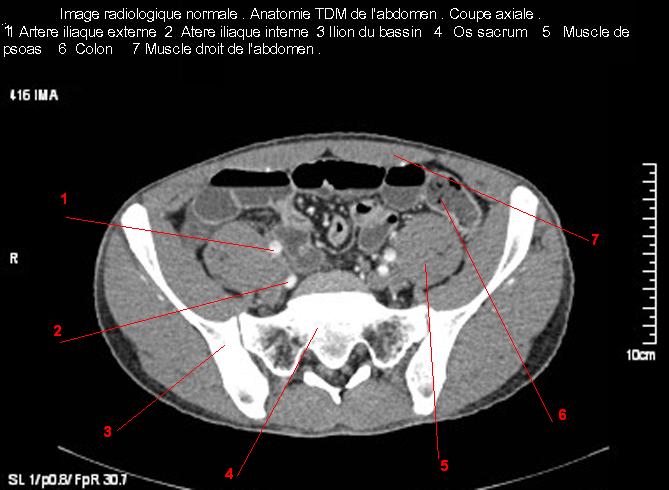

Image radiologique TDM normale de l'abdomen et tube digestif en coupe axiale ( CT scanner )  :

Coupe axiale     Coupe frontale      Coupe  sagitale